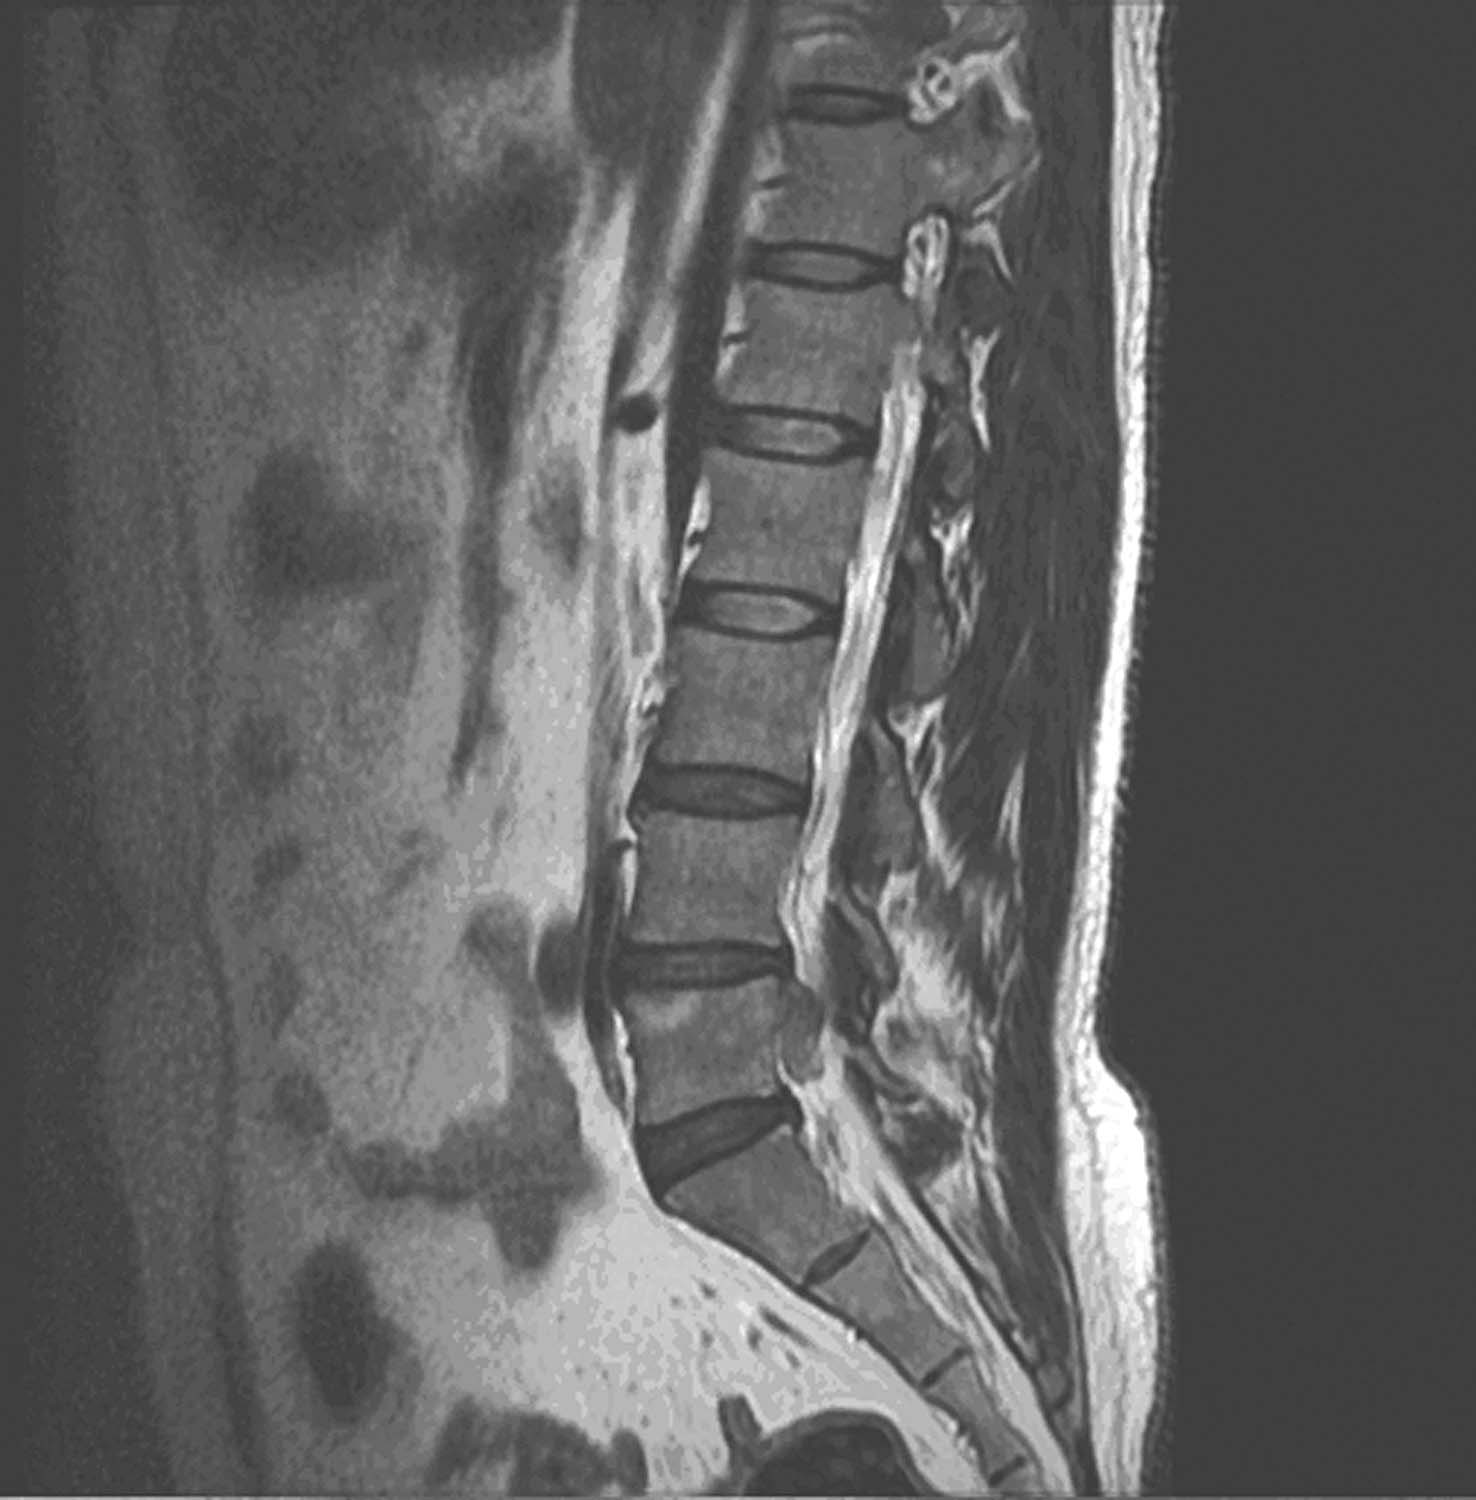

MRI可直接显示颈椎间盘突出部位、类型及脊髓和神经根受损的程度,为颈椎间盘突出症的诊断、治疗方法选择及预后提供可靠依据,是目前诊断颈椎间盘突出症最好影像学检查方法。矢状面T 1 加权像见突出椎间盘呈舌状向后方伸出,其信号强度与该椎间盘的信号相同或略低。可清晰显示硬膜外脂肪线截断、移位及硬膜囊和脊髓的受压等情况;T 2 加权像可见突出的髓核呈等、稍高或稍低信号(比脑脊液低,比脊髓高)。并可清晰显示突出部位蛛网膜下腔变窄、上下脑脊液梗阻情况及脊髓内有无缺血灶及脊髓空洞等情况;轴位可见脊髓及神经根受压,有无纤维环破裂及纵韧带断裂等征象,还能显示脱出的髓核组织与椎间盘分离,位于椎间盘平面上方或下方的椎管内,其内部信号强度类似原椎间盘的信号强度。对于椎管内游离髓核,Gd—DTPA增强扫描显示游离的髓核不强化,周围组织合并炎性反应时,可出现边缘反应性强化。